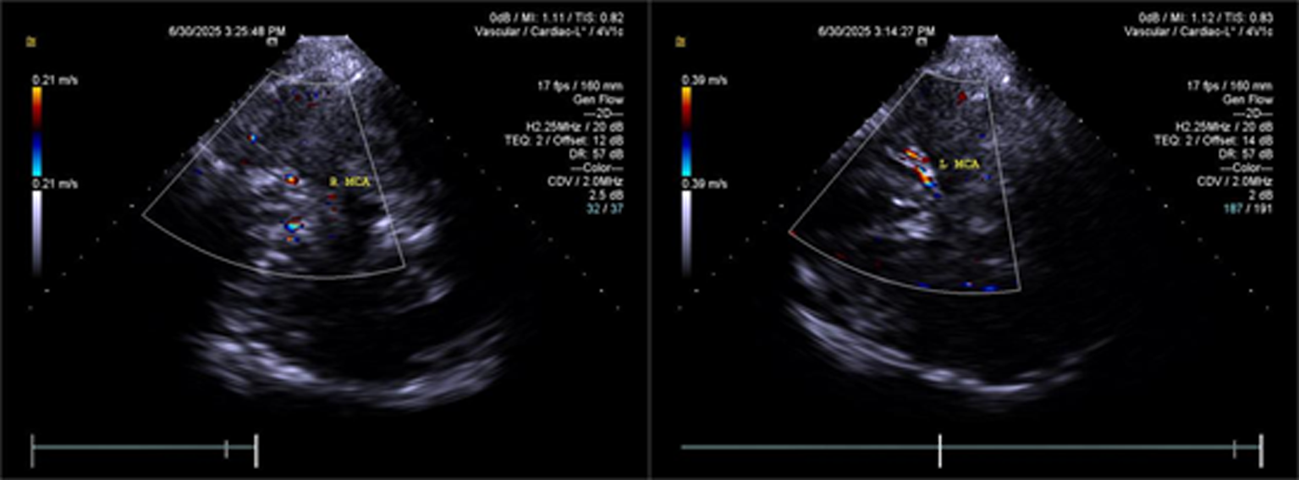

Objective To summarize diagnostic and differentialdiagnostic approaches for initial detection of moyamoya disease (MMD) using carotid ultrasound (CAU). Methods We report two patients who were first diagnosed with MMD by CAU and summarize the diagnostic reasoning and differential considerations. Relevant literature was reviewed to contextualize these findings. Results Case 1: A 57-year-old female presented with a >10 year history of dizziness and headache with recurrence over 3 days. CAU showed a reduced diameter of the left internal carotid artery (ICA), decreased flow velocity, and a lower resistance index, raising suspicion for severe intracranial stenosis or occlusion and prompting clinical exclusion of MMD. Magnetic resonance angiography (MRA) confirmed severe stenosis of the left ICA with absent distal branches and multiple small abnormal vascular networks in the left suprasellar region, consistent with MMD. Case 2: A 23-year-old male presented with dizziness for >1 year and transient right upperlimb weakness for 1 day. CAU and transcranial color Doppler (TCCD) showed a narrowed right ICA with reduced flow velocity and increased resistance index, suggesting chronic occlusion of the right middle cerebral artery and stenosis of the left middle cerebral artery, raising the possibility of MMD. MRA demonstrated an indistinct right ICA and right middle cerebral artery and narrowing of the left middle cerebral artery. On followup, the patient was diagnosed with MMD. Conclusion When CAU reveals a small internal carotid artery diameter accompanied by slowed flow velocity, clinicians should perform a comprehensive evaluation-including TCCD and further vascular imaging-to avoid missed or incorrect diagnoses of MMD.